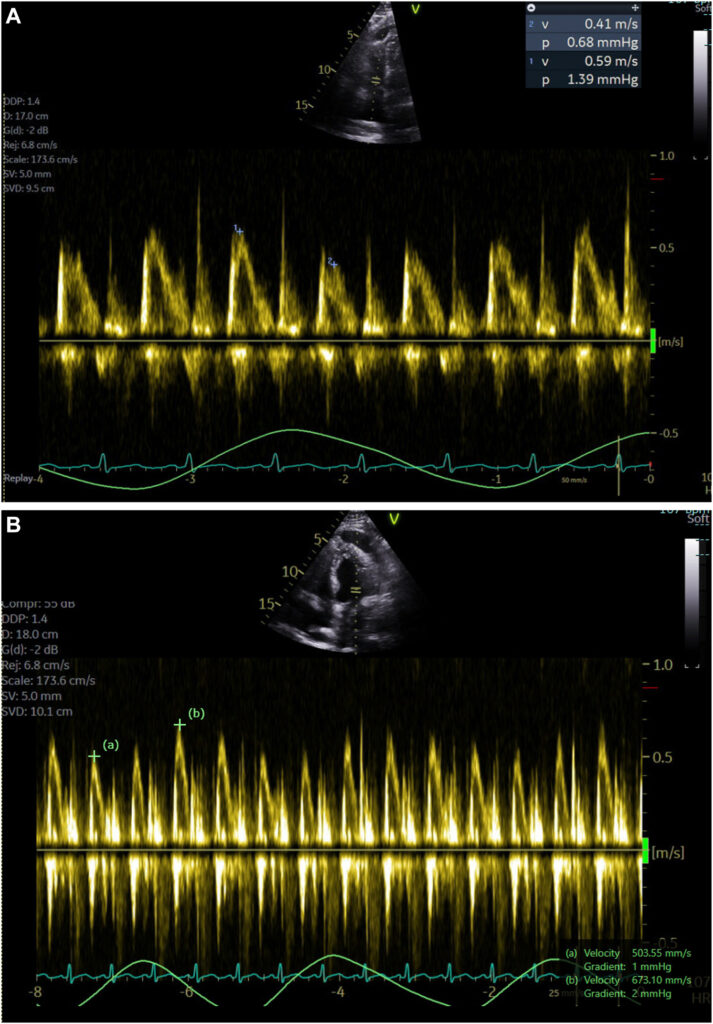

Havia ainda uma variação importante, durante o ciclo respiratório, nas velocidades dos fluxos tricúspide (aumento de 44% durante a inspiração) e mitral (redução de 25% durante a inspiração).

Durante a inspiração, a velocidade de pico do fluxo na via de saída do VE reduzia 28% (0.75 –> 0.54 m/s).

A VTI, avaliada na janela apical 3C, foi de 8.8 cm para 6.2 cm, conferindo uma redução de 30% durante a inspiração. Tal achado é consistente com a variação inspiratória do volume sistólico ejetado. A veia cava inferior estava pletórica (2.3 cm) com variabilidade inspiratória de 22%. Ainda, havia fluxo reverso na veia hepática durante a expiração.